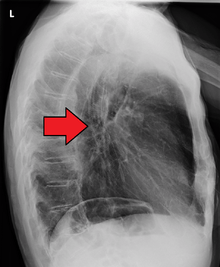

Additional testing is needed to assess how much the cancer has spread (see #Staging, below). Computed tomography (CT) of the chest, abdomen and pelvis can evaluate whether the cancer has spread to adjacent tissues or distant organs (especially liver and lymph nodes). The sensitivity of a CT scan is limited by its ability to detect masses (e.g. enlarged lymph nodes or involved organs) generally larger than 1 cm. Positron emission tomography is also used to estimate the extent of the disease and is regarded as more precise than CT alone. Esophageal endoscopic ultrasound can provide staging information regarding the level of tumor invasion, and possible spread to regional lymph nodes.

Contrast CT scan showing an esophageal tumor (axial view)

Contrast CT scan showing an esophageal tumor (coronal view)